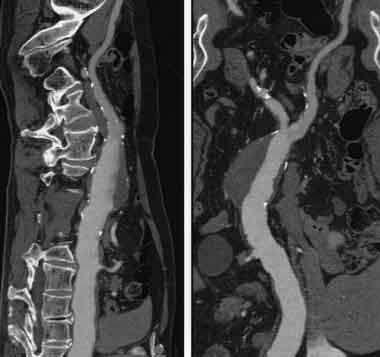

Проводим диагностику и лечение грыж любой формы межпозвонкового диска с помощью метода лазерной вапоризации.

Метод лазерной вапоризации выполняется, как правило, в амбулаторных условиях с использованием местной анестезии + внутривенное потенцирование. Чаще для местной анестезии используется 1% раствор лидокаина.

Под воздействием лазерного луча на конце световода создается высокая температура (от 200 до 400oС). Это приводит к образованию газа и пара, который выходит наружу через просвет иглы. При этом понижается внутридисковое давление, диск как бы сморщивается и грыжа, под действием возникающего «вакуум-эффекта», а так же, эластичности сохранившихся слоев фиброзного кольца и задней продольной связки, втягивается.

В этом и состоит основной смысл лазерной вапоризации или нуклеопластики. Как правило уже в процессе выпаривания больные отмечают уменьшения боли в пояснице.

Все вышеизложенные методы диагностики проводятся с помощью Мультисрезового спирального компьютерного томографа Toshiba (Asteion Super 4) - 26 декабря 2006 года выпуска, который находится на базе 19-й городской больницы.

Томограф фирмы TOSHIBA позволяет не только ставить точный диагноз, но и эффективно лечить пациентов: являясь новатором в технологии КТ, фирма TOSHIBA первая разработала возможность КТ – рентгеноскопии в реальном времени ( КТ – флюороскопия). КТ – это навигация в реальном времени, т.е. специальная флюороскопическая программа дает хирургу возможность проводить пункцию или пункционную биопсию образований, следя за продвижением иглы на экране томографа в реальном времени. Это полностью исключает нежелательное повреждение жизненно важных структур и обеспечивает точность попадания в заданную цель с точностью до 1 мм. Уже сегодня специалисты Центра Эндоскопической нейрохирургии, первыми в Украине, успешно делают бескровные пункционные операции на позвоночнике под контролем компьютерного томотрафа, так называемые пункционная вертебропластика – это когда под контролем томографа в тело поражённого позвонка вводится специальный костный цемент, который через несколько минут застывает. Это эффективный метод предупреждения и лечения патологических переломов позвонков при гормональном остеопорозе и гемангиоме тел позвонков.